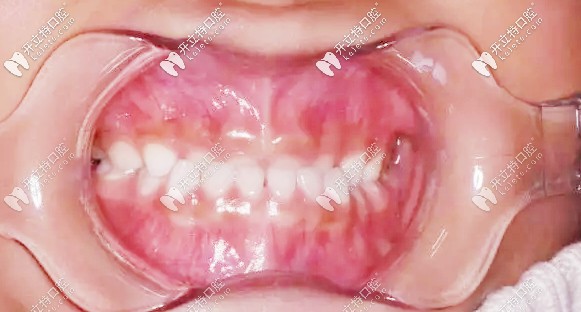

矯正前牙齒地包天

第二次復(fù)診,孩子的牙齒改善很明顯,我這顆懸著的心也算是能稍稍放下了▼

二次復(fù)診牙齒狀況